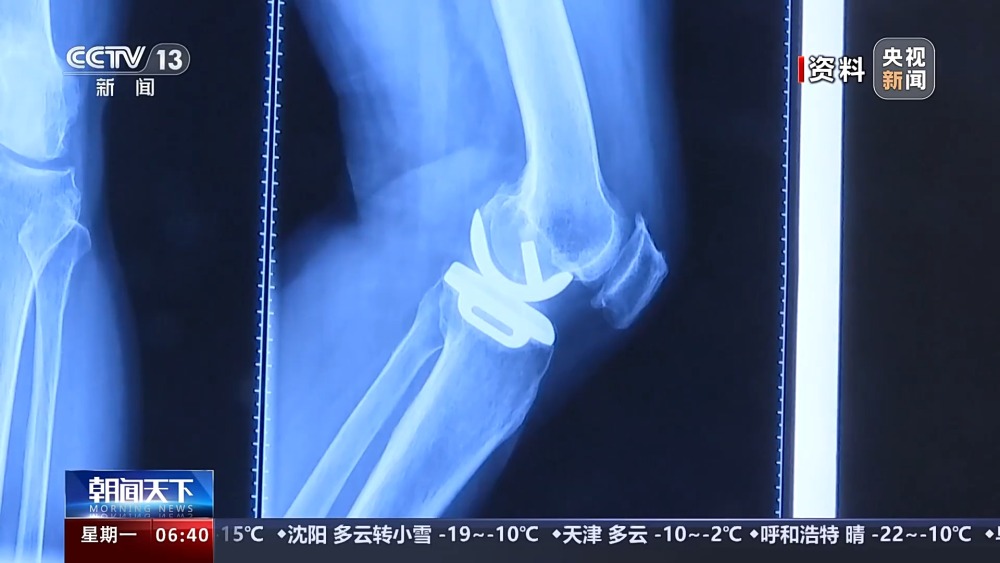

目前,我国有超过1亿人患有骨关节炎,65岁以上人群中,骨关节炎发病率接近50%。以前,严重骨关节炎患者主要通过膝关节置换手术来维持行走等基本功能。膝关节置换手术存在术后关节僵硬、长期疼痛等问题。保膝治疗包括药物、理疗等保守治疗,以及手术治疗。

保膝手术主要包括截骨术和单髁置换术,其中截骨术在解决患者疼痛症状的同时,阻止下肢异常应力对膝关节的进一步损伤,膝关节内所有软骨韧带、半月板都得到了保留。内侧单髁置换术,使膝关节外侧健康的软骨和半月板得到了保留,膝关节内外侧的韧带维持原有状态,患者康复后,拥有正常的膝关节功能。